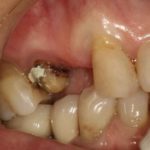

Заметить проблему можно намного раньше, чем она даст о себе знать. Так, во время гигиены ротовой полости можно увидеть, что около некоторых зубов ткани начали немного провисать. Или наоборот, может обнажиться шейка резца. Ясно одно: с мягкими поверхностями что-то происходит. Одновременно человек ощущает дискомфорт, внезапно возникающий после приема холодной или горячей пищи. Уже сейчас важно быстрее обратиться к врачу, чтобы узнать, почему проваливается десна, и что с этим делать. Доктор может найти причину в следующем:

- пародонтоз в запущенной стадии.

Если провалилась десна, врач всегда сначала удаляет зубной камень, когда это необходимо. Дело в том, что даже при регулярной гигиене остаются зоны, которые человек очищает ненадлежащим образом. Со временем там скапливается грязь, налет. Последний накапливает частички пищи, бактерии. Со временем он твердеет, образуя зубной камень, давящий на корни зубов. Образуются микропорезы, через которые попадает инфекция. Поэтому мягкие области могут воспалиться.